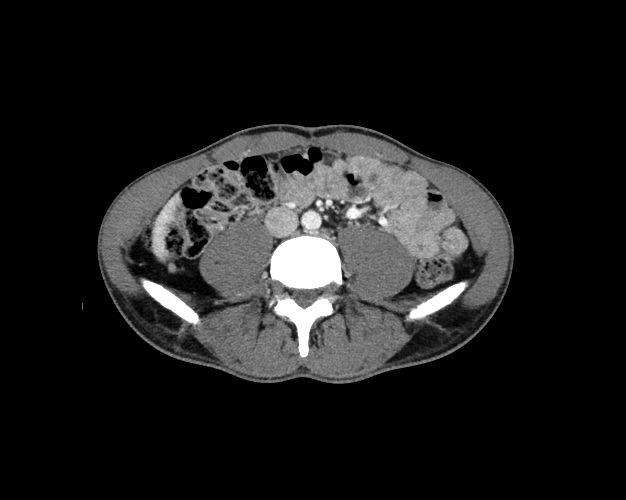

Body

Covers abdominal CT anatomy.